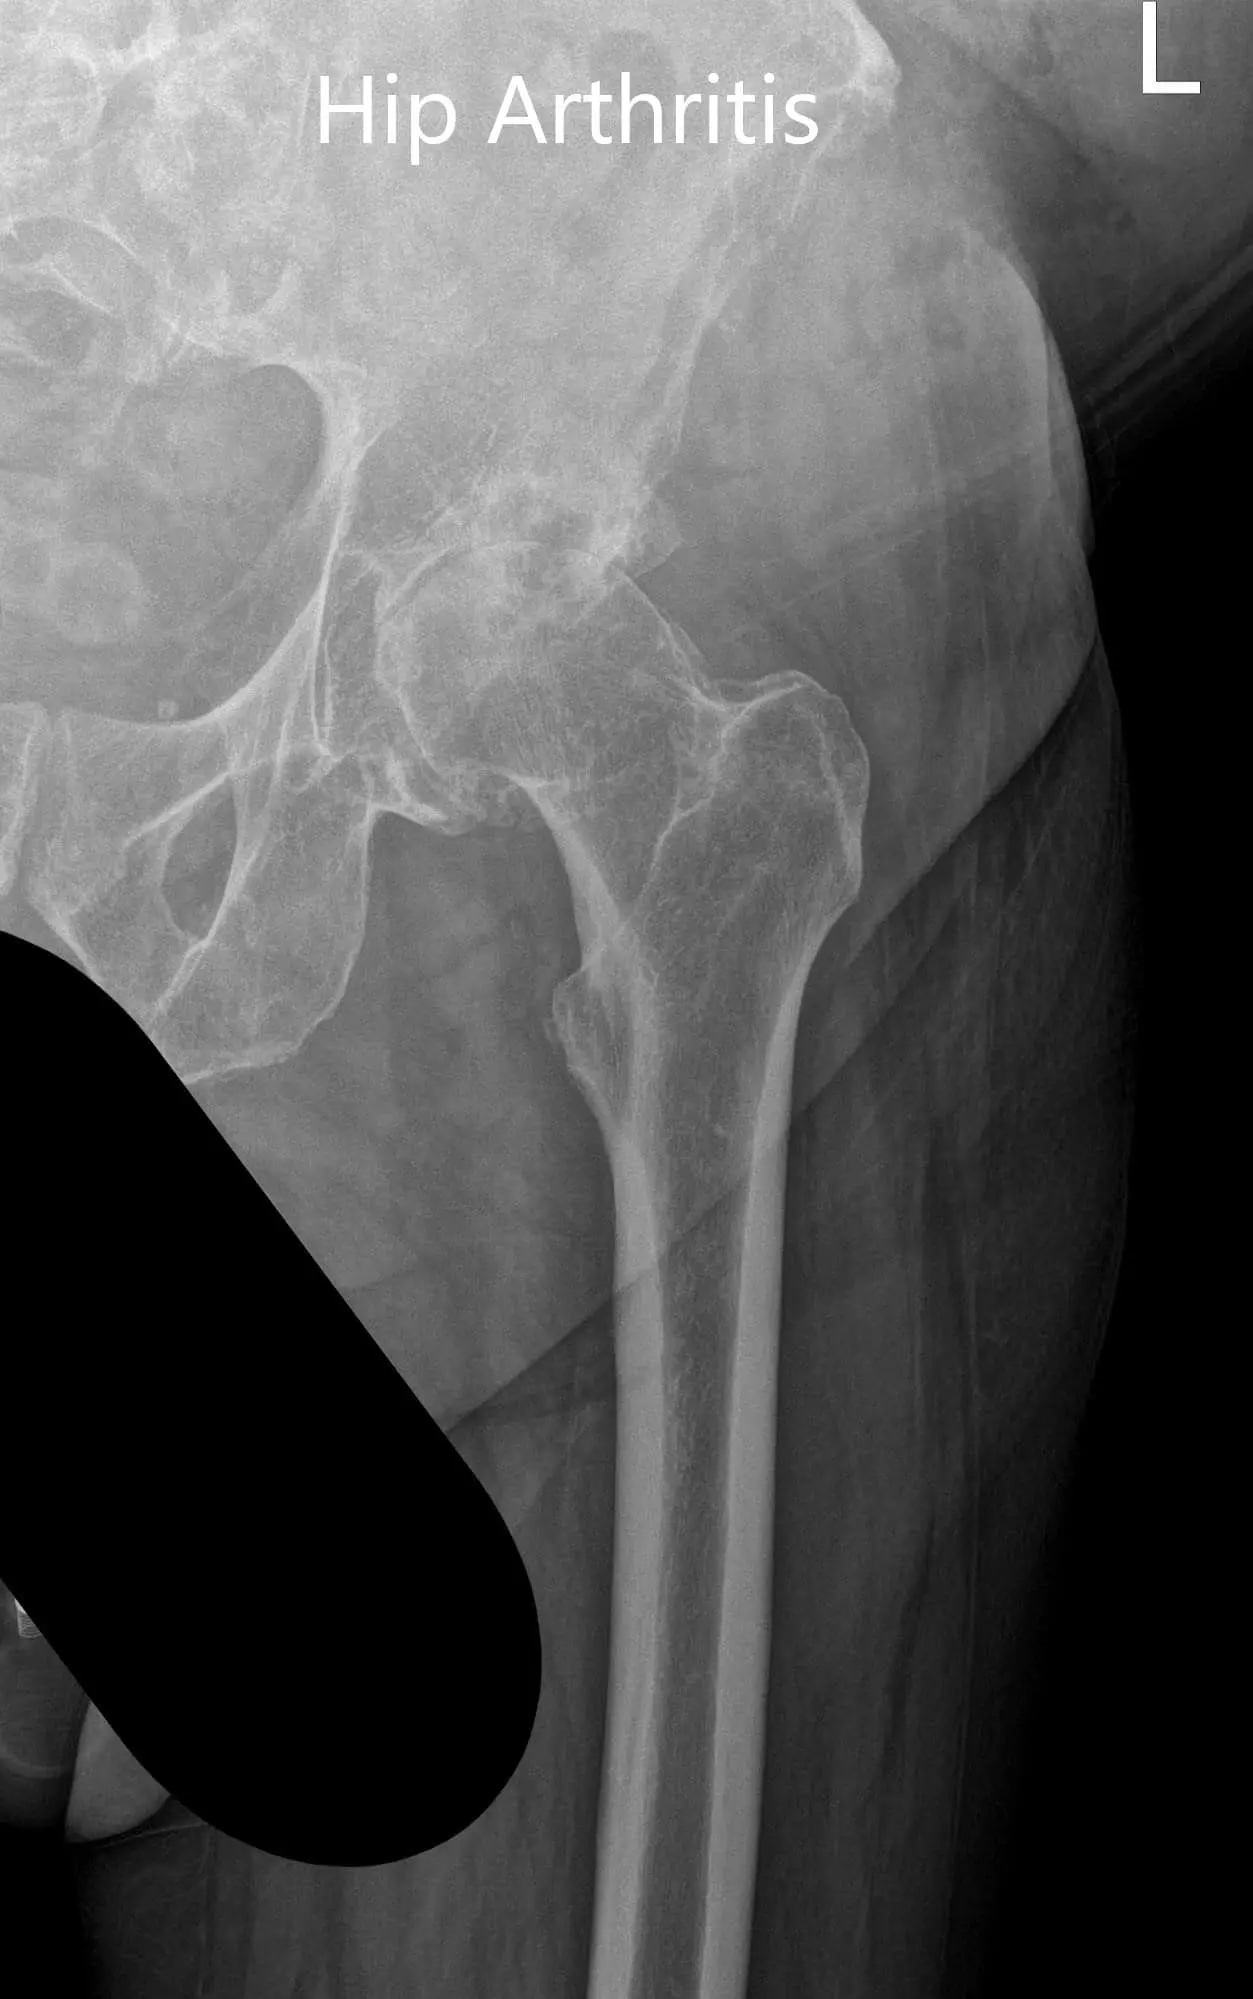

Preoperative X-ray showing the frog-legged lateral and AP view of the left hip 2

Preoperative X-ray showing the frog-legged lateral and AP view of the left hip

Preoperative X-ray showing the frog-legged lateral and AP view of the left hip - img 2

Preoperative X-ray showing the frog-legged lateral and AP view of the left hip.